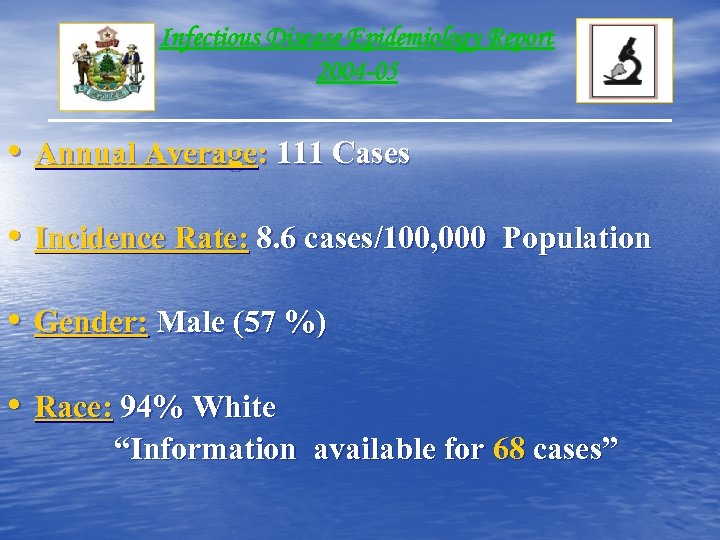

Infectious Disease Epidemiology Report 2004 -05 • Annual Average: 111 Cases • Incidence Rate: 8. 6 cases/100, 000 Population • Gender: Male (57 %) • Race: 94% White “Information available for 68 cases”

Infectious Disease Epidemiology Report 2004 -05 • Annual Average: 111 Cases • Incidence Rate: 8. 6 cases/100, 000 Population • Gender: Male (57 %) • Race: 94% White “Information available for 68 cases”